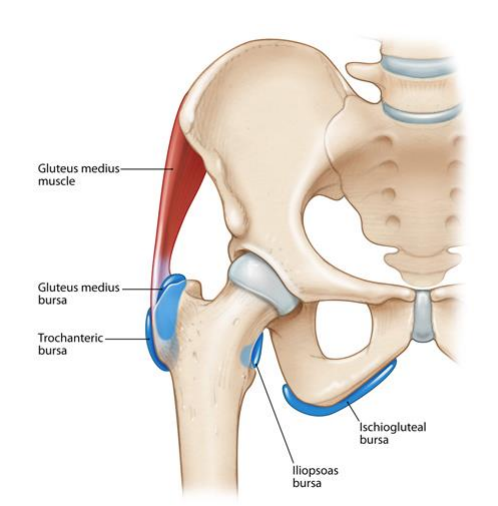

Hip bursitis, also referred to as trochanteric bursitis, is a condition where the bursa located over the bony prominence on the outer side of the hip (the greater trochanter) becomes inflamed. This inflammation can cause persistent pain and tenderness on the outside of the hip, often worsening with activity or when lying on the affected side.

While it frequently affects middle aged and older adults, hip bursitis is also seen in active individuals such as runners, footballers, and dancers, particularly due to repetitive strain or biomechanical stress on the hip. The bursae are small, fluid-filled sacs that reduce friction between bones, tendons, and muscles.

When they become irritated or overloaded, they can swell and become painful, a condition known as bursitis.

Hip bursitis, or trochanteric bursitis, occurs when the bursa over the outside of the hip becomes irritated and inflamed. This bursa normally acts as a cushion between the bony point of the hip (the greater trochanter) and the muscles and tendons that pass over it. When this cushioning structure is subjected to excessive friction or pressure, it can swell and become painful.